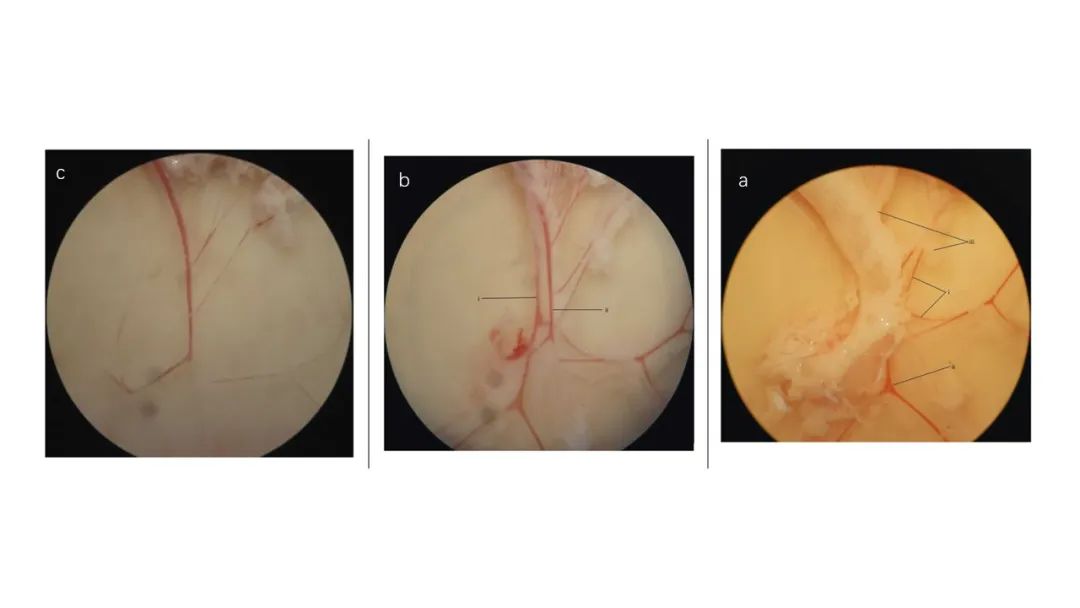

腸系膜血管解剖顯微鏡下圖像。(a)去除結締組織和神經束前,可見(i)動脈、(ii)靜脈和(iii)粘附脂肪。(b)切除大部分結締組織和神經束后。(i)位于(ii)靜脈下方的動脈比后者顯得“更白”。(c)清潔的動脈。

本研究表明PSAE對SHR的降壓作用可能是通過提高阻力動脈NO水平和降低阻力動脈ET-1水平來改善內皮功能障礙。這種效果可能是由于該植物具有較高的抗氧化性能,盡管這需要更深入的研究來證明。本研究還表明,每日給予一次PSAE的效果可能并不優(yōu)于全劑量培哚普利。因此,需要進一步研究PSAE對SHR的“雙劑量”(BD),以闡明PSAE是否具有與全劑量培哚普利相當的抗高血壓作用。將植物提取物與全劑量培哚普利聯合使用,還需要進一步研究,以評估添加植物是否會產生更有益的效果。證實了培哚普利與植物的協(xié)同作用及其輔助處理的能力。此外,大樣本量和良好方法學質量的meta分析試驗將有助于為PSAE輔助治療原發(fā)性高血壓的有效性和安全性提供一個明確的結論。最后,為了將PSAE應用于人類,還需要對PSAE長期攝入的長期影響進行研究,以及臨床研究。